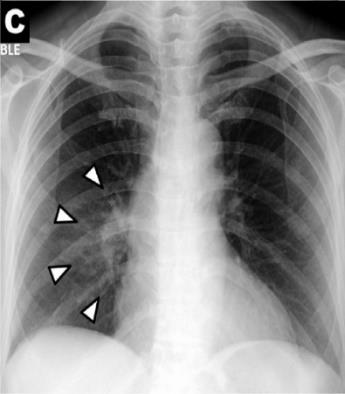

Federated Learning (FL) is a suitable solution for making use of sensitive data belonging to patients, people, companies, or industries that are obligatory to work under rigid privacy constraints. FL mainly or partially supports data privacy and security issues and provides an alternative to model problems facilitating multiple edge devices or organizations to contribute a training of a global model using a number of local data without having them. Non-IID data of FL caused from its distributed nature presents a significant performance degradation and stabilization skews. This paper introduces a novel method dynamically balancing the data distributions of clients by augmenting images to address the non-IID data problem of FL. The introduced method remarkably stabilizes the model training and improves the model's test accuracy from 83.22% to 89.43% for multi-chest diseases detection of chest X-ray images in highly non-IID FL setting. The results of IID, non-IID and non-IID with proposed method federated trainings demonstrated that the proposed method might help to encourage organizations or researchers in developing better systems to get values from data with respect to data privacy not only for healthcare but also other fields.